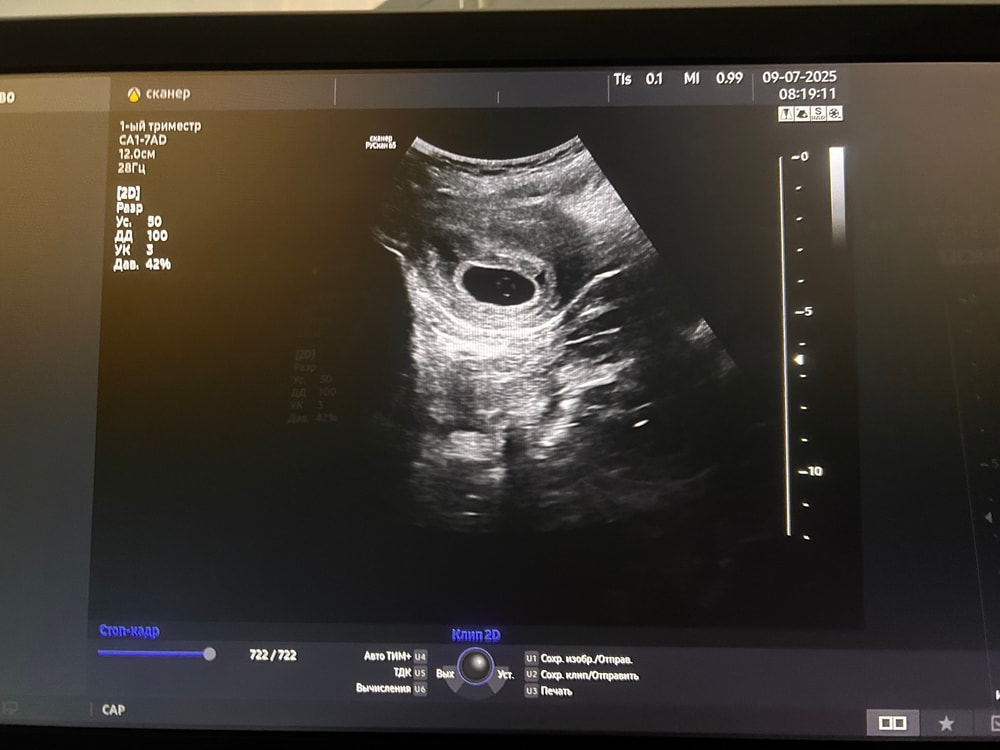

фото с узи Изображение

Анэмбрионию ставят, когда плодное яйцо >25мм. У Вас сколько? Желточный мешочек - хороший прогностический признак, скоро и эмбрион появится, верьте в малыша 🙏

Анастасия, плодное 7.8

Olga, 2.8 мм желточный мешок